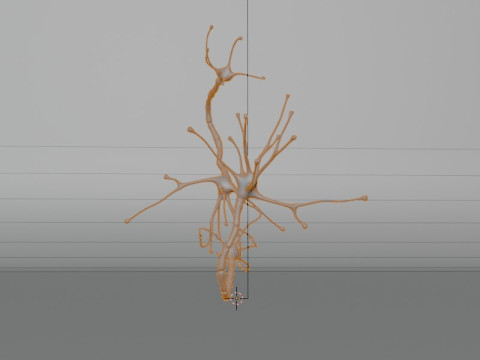

Neuron Sel Saraf Realistis Low-poly Model 3D

Neuron Sel Saraf Realistis Model 3D blend, png, Dari 3dcreations

A highly detailed and realistic 3D model of a human nerve cell (neuron), showcasing dendrites, axon, and synaptic terminals with scientific accuracy. Perfect for anatomy study, educational visualization, and medical simulations.

⚙️ Key Features:

Realistic and scientifically accurate nerve structure

Includes detailed axon, dendrites, and cell body

Ideal for educational and medical 3D projects

Smooth mesh topology for easy rendering and animation

Suitable for VR, AR, and scientific visualization

High-quality texture and proportionally accurate modeling